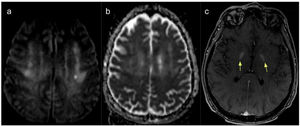

A CT scan revealed no alterations; however, as neurological symptoms persisted at 10 days after admission, he underwent a brain MRI scan, which revealed hyperintensities on T2-weighted sequences in both cerebellar hemispheres (dentate nuclei), particularly on the right side, with restricted diffusion on DWI sequences. We also observed a hyperintense focus in the left corona radiata, with diffusion restriction on diffusion sequences and a small area of blood deposition in the left cerebellar hemisphere. Post-contrast sequences revealed contrast uptake in the cerebellar lesions and globi pallidi (Figs. 1 and 2).

These findings are compatible with ischaemic and haemorrhagic processes in the context of heat stroke.

The interest of our case lies in the rarity of the clinical presentation and the presence of the classic cerebellar lesions, particularly lesions to the dentate nuclei (secondary to Purkinje cell destruction) with blood deposition, in addition to lesions to the corona radiata and basal nuclei, which showed contrast uptake; these findings are compatible with current theories on the pathophysiology of the condition as an ischaemic or haemorrhagic process.